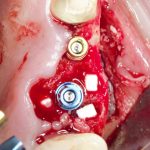

Изоляция области аутографта и имплантатов барьерной мембраной.

Перекрывать костный блок барьерной мембраной или оставить так? По этому вопросу есть много мнений. Между тем, в публикации по методике есть ясное показание, когда это требуется.

Конкретно в этом клиническом случае между костным аутотрансплантатом, ложем и имплантатами есть пустое пространство. Если его не изолировать от мягких тканей, они прорастут и осложнят интеграцию аутографта. Поэтому я решил перекрыть костный блок барьерной мембраной, пусть это делает хирургическую операцию немного дороже.

— я использовал барьерную мембрану Geistlich Bio-Gide, которая имеет две разные поверхности: с одной стороны она рыхлая «адгезивная», с другой — гладкая и прочная. Как укладывать — на результат не влияет, но в плане удобства рыхлую поверхность мы «приклеиваем» к тому, на чем требуется барьерную мембрану удержать. В данном случае хотелось бы удержать её на костной поверхности — следовательно, мы укладываем её рыхлой поверхностью к кости.

— много лет мы используем антибиотики для интраоперационной профилактики инфекционно-воспалительных осложнений. Уже в то время мы пришли к выводу, что удобнее всего — порошки антибактериальных препаратов для приготовления раствором: дешевые, стерильные, в удобной упаковке. Прямо в виде порошка их можно добавлять в графт, растворы для ирригации, либо использовать так, как показано на фото. Еще мы используем порошок антибиотика для изготовления пасты, которой обрабатываем имплантаты в процессе ревизии или при лечении периимплантита. Это удобнее и эффективнее, чем интраоперационное использование жидких форм антибактериальных препаратов.

— ты знаешь, что барьерная мембрана может выполнять две функции, каркасную и изолирующую. Первая функция требует обязательной фиксации и натяжения, вторая — нет. В нашем случае «каркасом» регенерата является костный блок, а барьерная мембрана нужна только для изоляции. Поэтому она не требует натяжения и фиксации пинами.

После я внимательно проверил, что костный блок и имплантаты полностью перекрыты. Теперь рану можно ушивать.